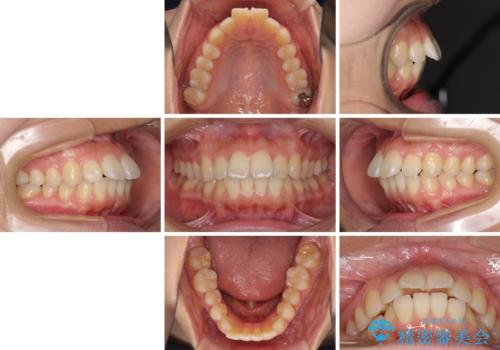

前に出ている前歯を引っ込めたい インビザライン矯正

- 前方に傾斜した上下の前歯を気にして来院された患者様です。

唇の閉じにくさや横顔のシルエットが気になるような突出感ではなかったため、インビザラインを用いて、歯列の遠心移動とIPR(歯と歯の間を削る)により前歯の傾斜を改善していくこととしました。

スムーズに終了すると思われましたが、インビザライン矯正独特の奥歯が咬み合わない状態が続き、更には遠方へ転居されたこともあり、治療期間は長引いてしまいました。